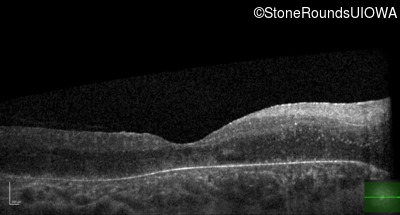

Age at visit: 17 years

This 17 year old female feels that the vision in her right eye has worsened since her cataract surgery 8 weeks ago.